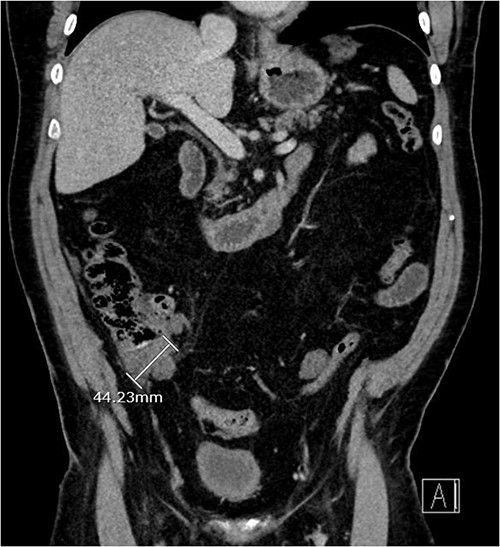

About 1 year later, the patient re-presented for anaemia and underwent a further CT scan. In the right iliac fossa, a 51.96 mm mass was noted such that the appendix could not be visualized separately, with a focus of calcification (Fig. 1). There was infiltration into the adjacent fat and abnormal soft tissue thickening of the peritoneal reflection along the right paracolic gutter. Multiple new peritoneal nodules in the upper abdomen were also identified (Fig. 2). The appearances were in keeping with disseminated malignancy. Following histological analysis, diagnoses of LAMN and PMP was made. The patient was initiated on mitomycin and capecitabine chemotherapy, which modestly reduced the size of the right iliac fossa mass from 51.96 mm to 44.23 mm (Fig. 3).

Three-month post-chemotherapy coronal CT abdomen and pelvis with contrast demonstrating a reduction in size of the primary appendiceal mass to 44.23 mm.